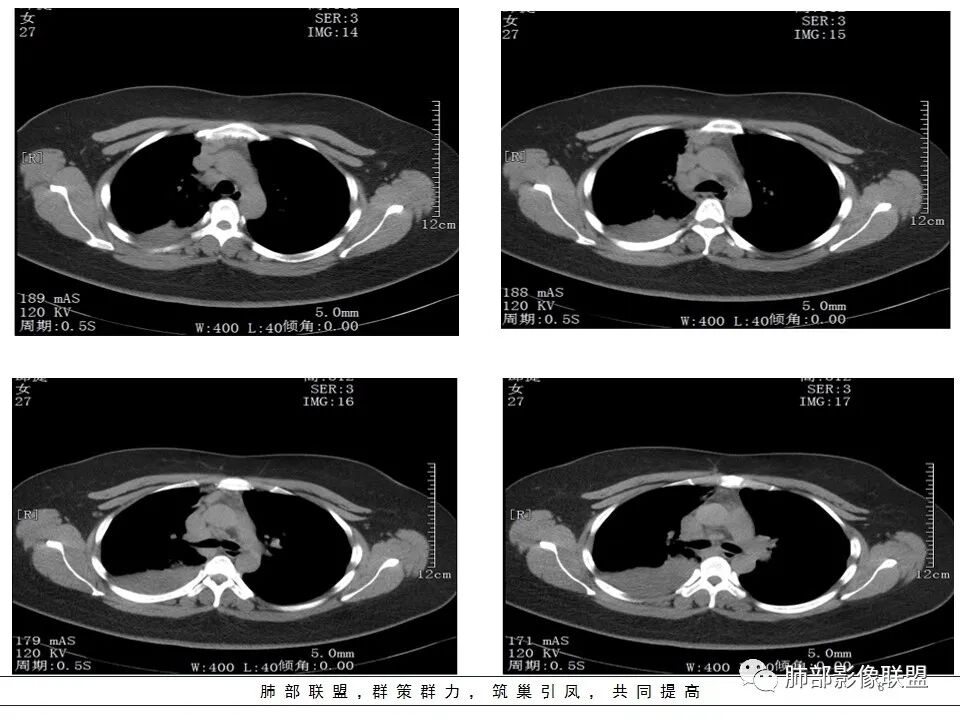

右肺体积缩小,右肺门可见片状影,叶支气管堵塞,呈低密度,无强化,其内似可见点状高密度钙化,病变外周膨隆,右肺下叶大片状致密影,增强后明显强化,其内血管走形自然,右肺下叶呈肺不张改变。纵隔肺门无肿大淋巴结。年轻女性,高热、黄痰来诊。综合考虑:右肺中、下叶综合征合并下叶肺不张,考虑炎性病变,炎性叶支气管阻塞可能性大,早期肺脓肿?结核有点不符合,无胸水,病灶形态太单一。

女,27岁,右肺下叶支气管闭塞,圆形软组织肿块和不张肺,增强不均匀强化,见片状坏死,多个纵隔淋巴结肿大,无钙化空洞及卫星灶;考虑恶性占位,肺肉瘤或鳞癌合并肺不张,鉴别诊断:结核,肺脓肿

从CT看难度大。女,27岁,发热6天,咳嗽咳痰3天。无呼吸困难。右中间支气管堵塞?右下肺不张,大支气管堵塞常见原因:结核、肿瘤、异物。无呼吸困难,感觉病程较长,肺不张导致的肺功能下降有一定耐受。堵塞支气管似见低密度病灶,强化不明显,粘液表皮样癌?腺样囊性癌?鳞癌?还是结核?有待支气管镜进一步检查。

年轻女性,发热6天,咳嗽咳痰三天

CT扫描示右肺下叶支气管堵塞,类圆形大肿块伴胸膜下大片肺实变影,增强扫描类圆形肿块延迟强化,见少量坏死,余实变区增强可见内部血管走行。纵隔见肿大淋巴结。考虑为恶性病变伴右肺下叶肺不张

水晶石头 :

患者青年女性,发热6 天,咳嗽、咳痰3天。为黄脓痰。胸部CT:右肺体积稍小,右中间支气管肿物堵塞,中叶、下叶大片实变不张,与正常肺组织分界清楚。增强实变影明显强化,右下肺支气管近心端见类圆形强化结节影,血管纤细,部分支气管显影变细,纵隔淋巴结肿大。结合无呼吸困难症状,病程长。综合考虑低度恶性病变并阻塞性肺炎,类癌可能大,鉴别结核、淋巴瘤。